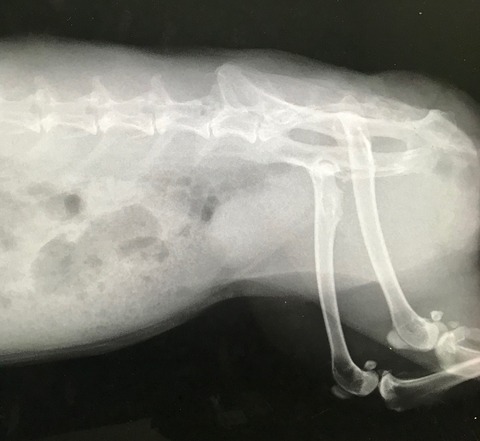

今回は普段の簡易健診にくわえてレントゲンもお願いしました。

ちょっと記憶にあるところで、保護後早々の避妊手術以降、

撮る機会がなかったとちゃうかな、と。

こないだのお腹不調も待合室で食べ始めたから、レントゲンに至らず。

心臓、胸周りほか、腎臓の方とか、一応、何か拾える変化がないか、と…。

所見、特に何って問題は見当たらず、体ん中も準備オーケーでした(。・m・)

レントゲンで見れるよう内臓脂肪もほぼなく健康的